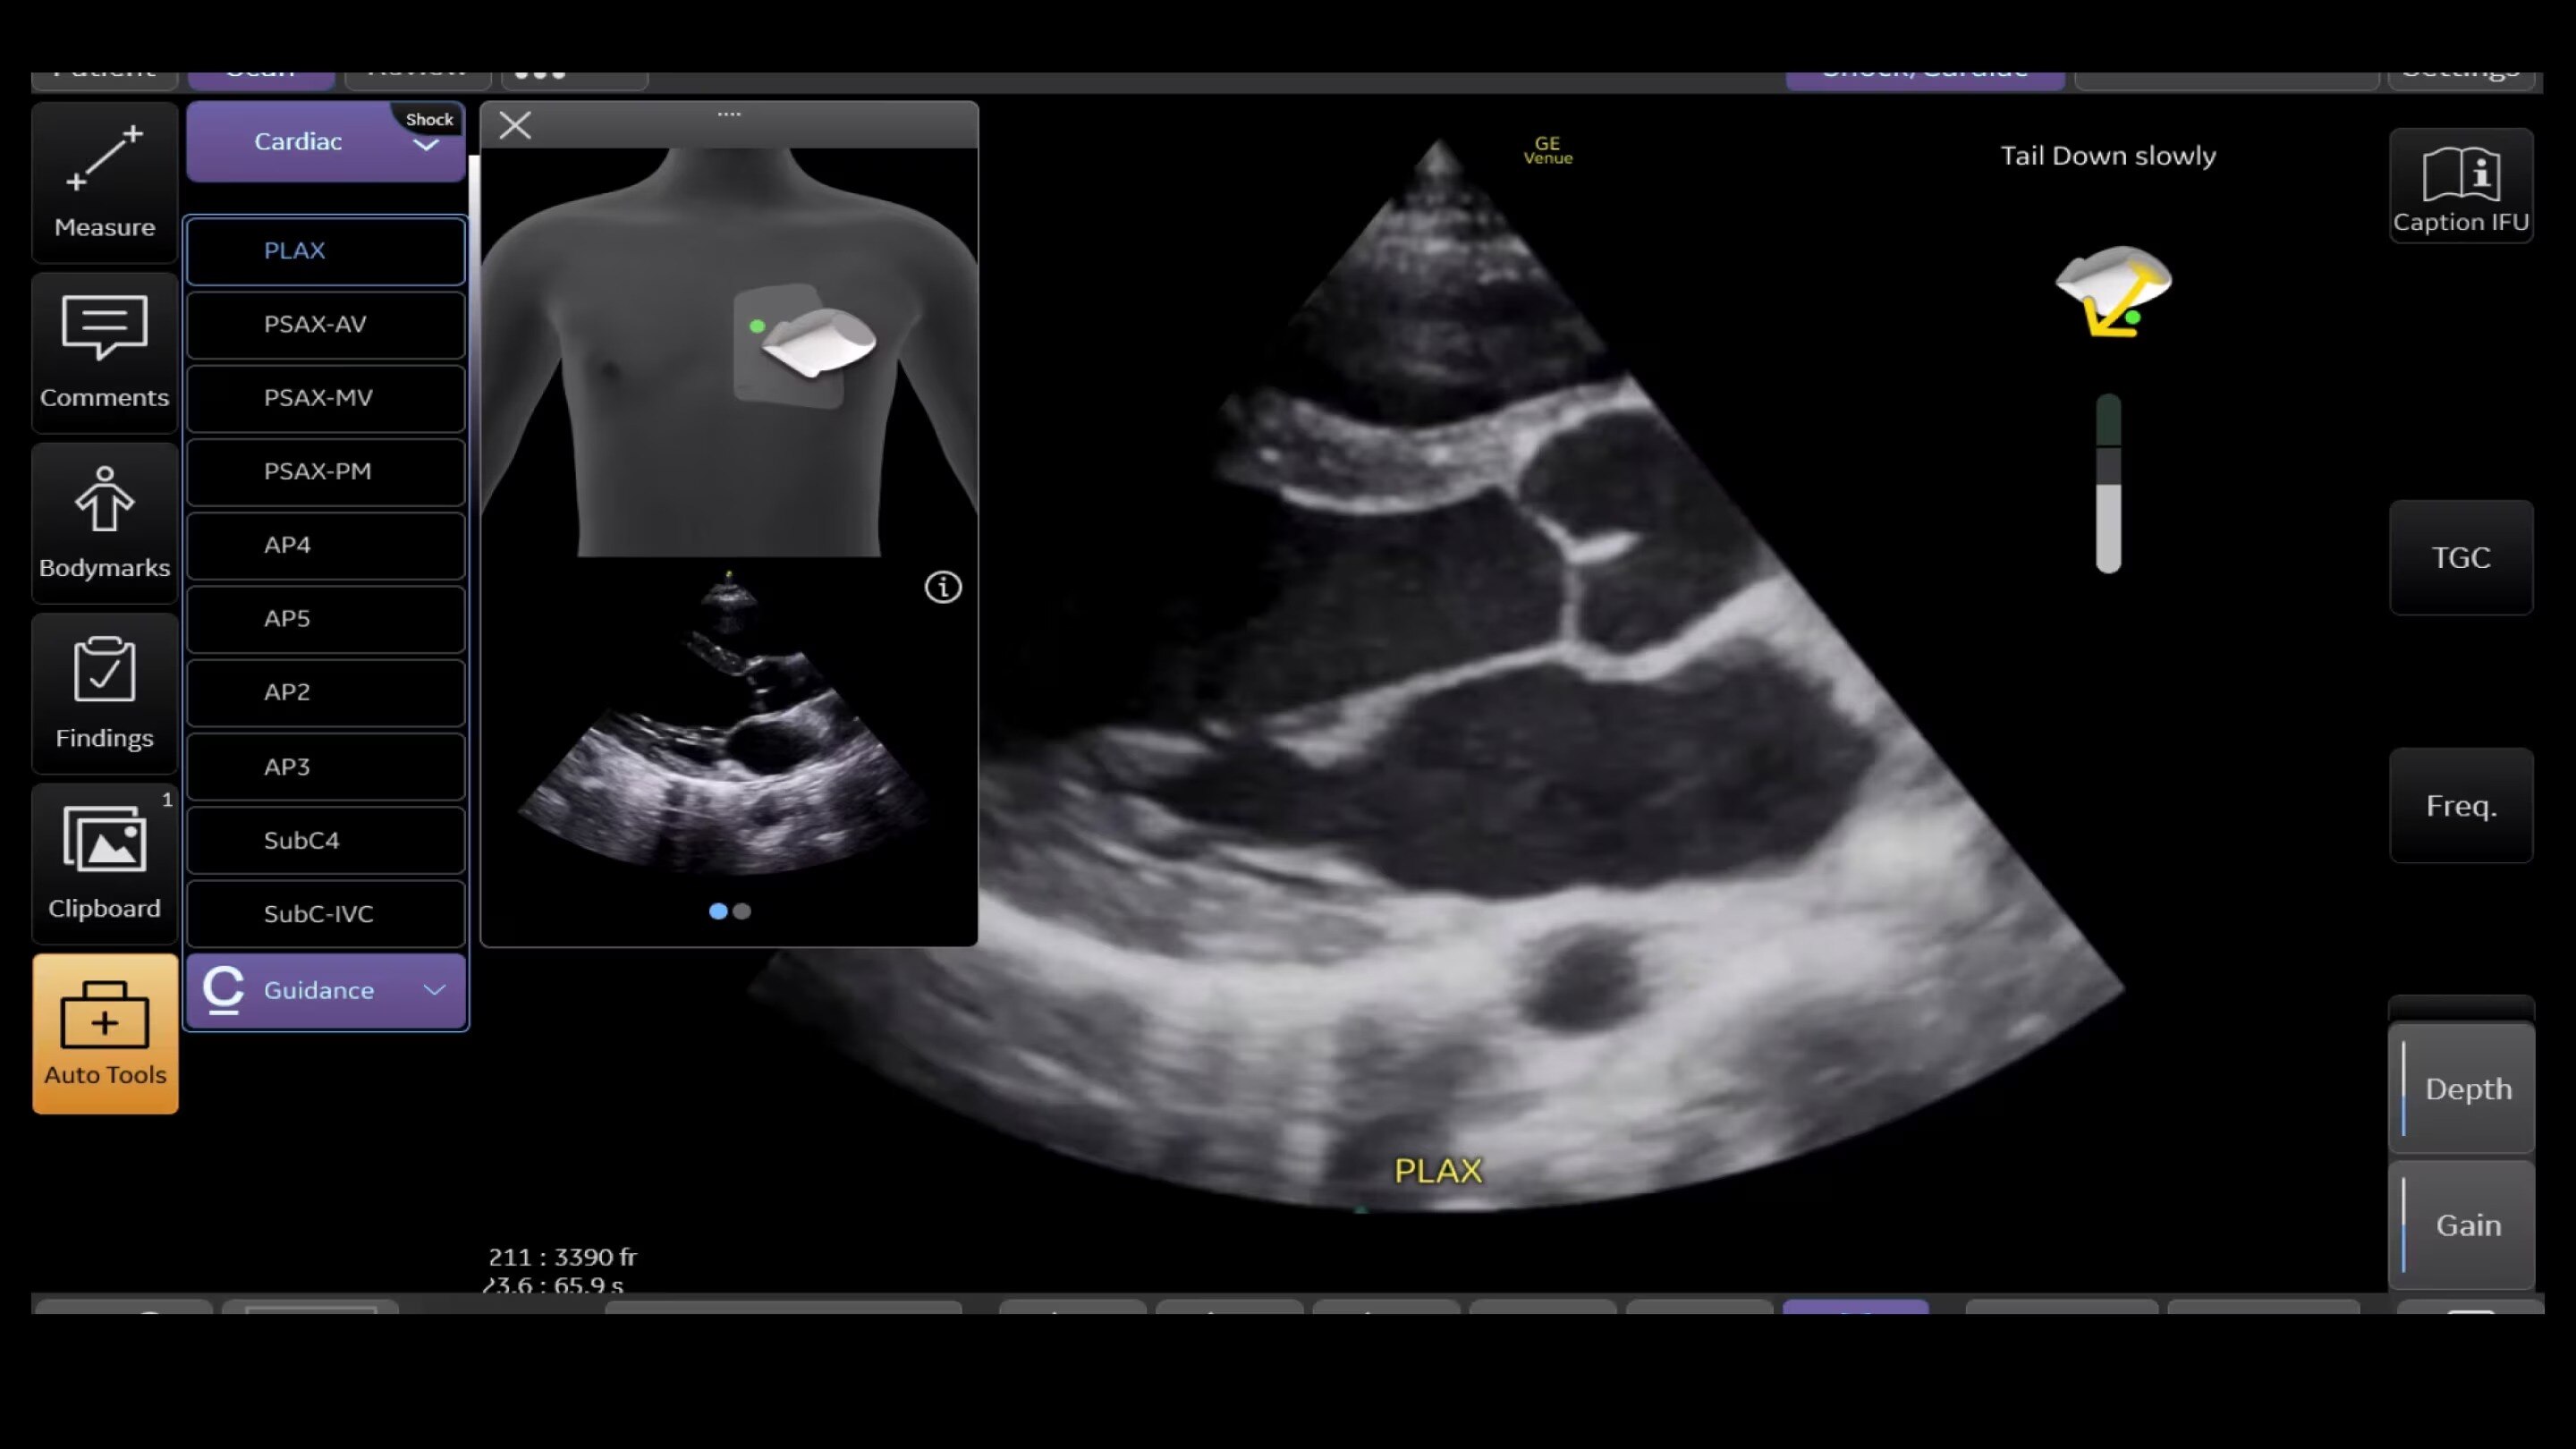

Caption Guidance

Scan with confidence: The right tool in the right hands for cardiac ultrasound in critical moments

Thanks to Caption Guidance™ AI-driven software on the Venue Family, even new POCUS users can capture diagnostic-quality cardiac images successfully. The on-screen, AI-based tool aids with turn-by-turn probe placement to capture the needed views.